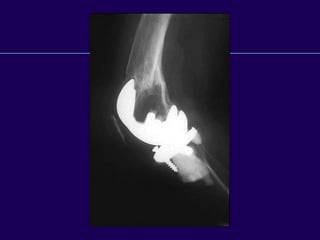

Supracondylar Fractures

After TKR

OSTEOPOROSIS

l Major trauma is not required to

produce fractures in many TKA

patients

l Alignment not correlated

with fracture

l Weight not a significant

Fractures After TKA

Neer Classification of Supracondylar

Fractures

l Type I - Minimal displacement

l Type IIA - Medial displacement of

condyles

l Type IIB - Lateral displacement

of condyles

l Type III - Supracondylar and shaft